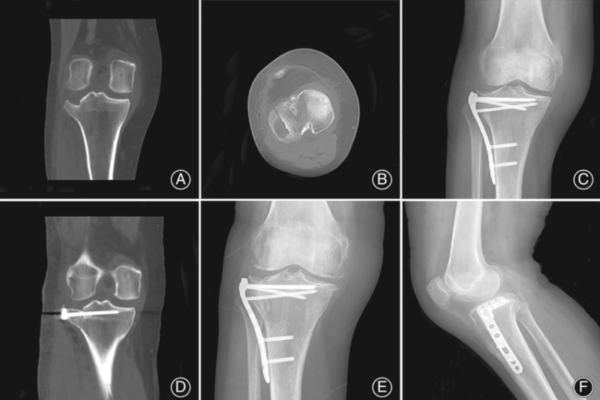

- Chụp cắt lớp vi tính (CT scan):

- Chỉ định: Trong hầu hết các trường hợp gãy mâm chày, CT scan là cần thiết để đánh giá chi tiết cấu trúc xương, đặc biệt là khi nghi ngờ gãy phức tạp, gãy lún, hoặc cần lập kế hoạch phẫu thuật.

- Ưu điểm: Hiển thị rõ ràng các mảnh gãy, mức độ lún của mâm chày, và sự xâm lấn vào khớp. Giúp phân loại gãy chính xác hơn và lựa chọn phương pháp điều trị phù hợp.

- Chụp cộng hưởng từ (MRI):

- Chỉ định: Khi nghi ngờ có tổn thương mô mềm phối hợp như rách dây chằng, tổn thương sụn chêm, hoặc tổn thương tủy xương.

- Nắn chỉnh hở và cố định trong (Open Reduction and Internal Fixation – ORIF):

- Phương pháp: bộc lộ ổ gãy, nắn chỉnh các mảnh gãy về vị trí giải phẫu ban đầu, sau đó cố định bằng nẹp vít (plate and screws) hoặc vít xốp (cannulated screws). Trong trường hợp gãy lún mâm chày, cần nâng mâm chày bị lún lên và ghép xương để phục hồi diện khớp và nâng đỡ sụn khớp.

- Các loại nẹp vít: Nẹp vít khóa (locking plate), nẹp vít tái tạo đường viền mâm chày (pre-contoured plate), nẹp vít bản rộng (buttress plate). Lựa chọn loại nẹp vít phù hợp tùy thuộc vào loại gãy và vị trí gãy.

- Ghép xương: Có thể sử dụng xương tự thân (lấy từ mào chậu) hoặc xương đồng loại để ghép vào vùng khuyết xương do lún mâm chày hoặc để tăng cường độ vững chắc của ổ gãy.